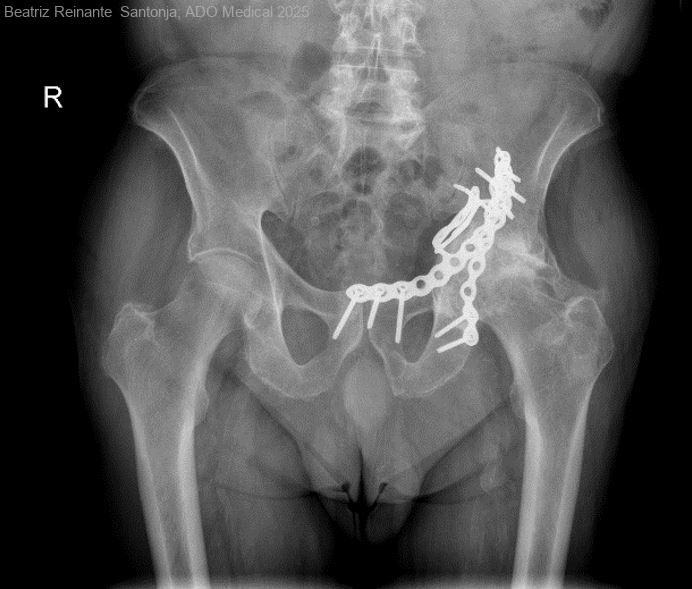

Varón de 72 años que acude a consultas externas de Traumatología por coxartrosis izquierda.

Como antecedentes el paciente presenta fractura de ambas columnas de cotilo izquierdo intervenido quirúrgicamente en 2018 tras accidente de tráfico. Se intervino realizando reducción...